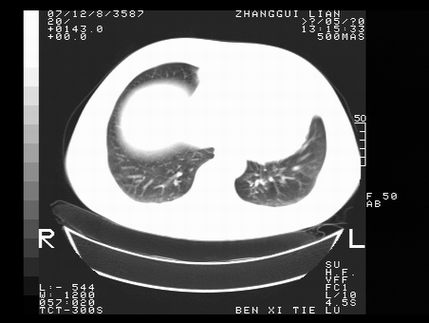

标题: CT10818:男,73,TB病史,现病史肺炎及直肠CANCER术后 [打印本页]

标题: CT10818:男,73,TB病史,现病史肺炎及直肠CANCER术后

这个请版主删除掉,这个病例我发过的,发重了,此人病史是,f,46y,胸疼,无其他原因就诊

左侧中央型肺癌伴阻塞性肺炎\\不张,左侧前上纵隔亦增宽,建议上传纵隔窗除外淋巴结转移.

考虑:左侧中央型肺癌伴阻塞性肺炎,纵隔淋巴结转移。

1)考虑为:左侧中央型肺癌伴阻塞性肺炎,纵隔淋巴结转移。2)双侧少量胸腔积液。3)心包积液。

左侧中央型肺癌伴阻塞性肺炎,纵隔淋巴结转移。

考虑左侧中央型肺癌伴阻塞性肺炎,纵隔淋巴结转移。